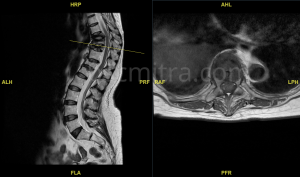

Diagnosis awal ditegakkan berdasarkan gejala klinis dan pemeriksaan penunjang. Pemeriksaan radiologis terdiri daro foto polos tulang belakang, MRI dan bila perlu CT Scan tulang belakang.